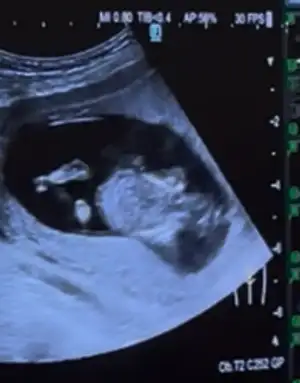

Bana da tahminde bulunabilirmisiniz? 11hafta 6günlükAy sanırım erkek bacak arasında bir çıkıntı var gibi görüyorumsağlıklı olsun inşallah sağlıkla gelsin dünyaya

Kimler kimler yazdı?Bana öyle gibi geldiYok bacak arasını tam açmadı

İçimden kız geliyo ya

Daha öncede denk gelmiştik galiba erkeğe benziyor demiştimBana da tahminde bulunabilirmisiniz? 11hafta 6günlük

12 haftadan küçük sanirimMrb tahminniz var mı acaba :)

Banada bakabilir misinizErkek bence sağlıklı dünyaya gelsin inşallah

16haftalık bacak arası. Tahmin varmı?Ay sanırım erkek bacak arasında bir çıkıntı var gibi görüyorumsağlıklı olsun inşallah sağlıkla gelsin dünyaya

Ay ben bunu kız görüyorum ya çıkıntı yok dümdüz duruyorMerhabaBenim bebeğimede tahminde bulunur musunuz rica etsem

Çok net değil maalesef ya16haftalık bacak arası. Tahmin varmı?